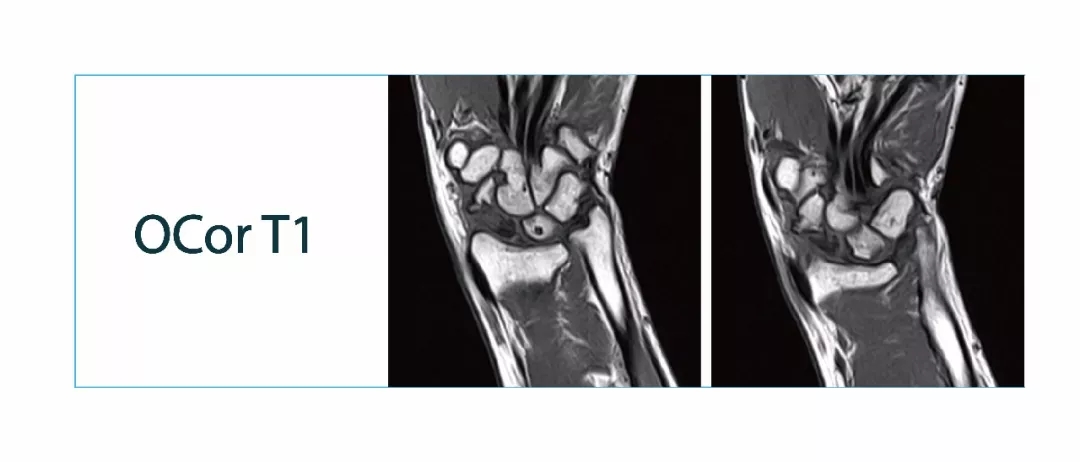

【朗润影像档案】磁共振影像病例分享(编号20180126)